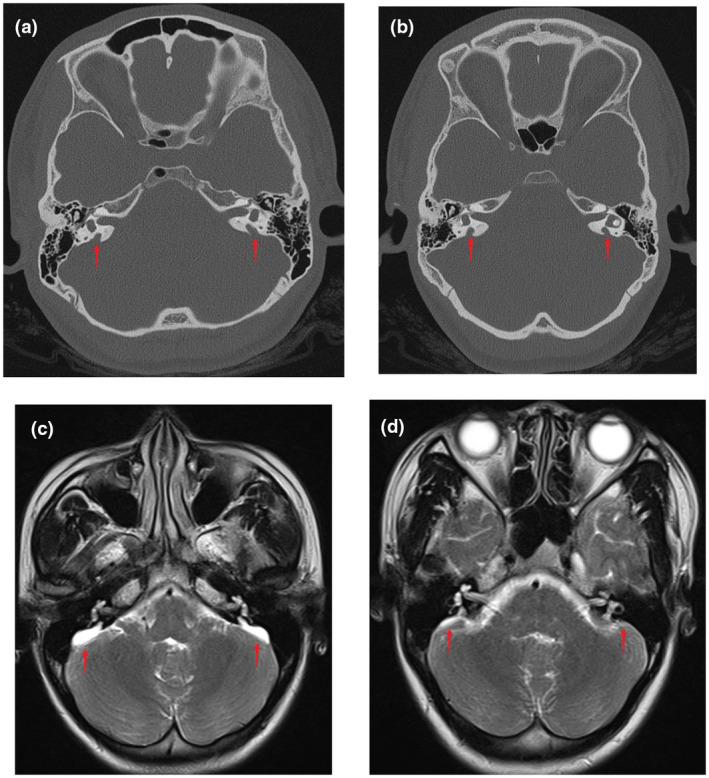

Hearing loss in the twins with EVA was diagnosed using auditory tests and imaging examinations. Two pathogenic mutations, c.919-2A>G and c.1614+5G>A were detected in SLC26A4, the latter of which has not been reported in the literature. The minigene expression in vitro confirmed that c.1614+5G>A could cause aberrant splicing, resulting in skipping over exon 14.

通过听觉测试和影像学检查对双胞胎的 EVA 听力损失进行了诊断。在 SLC26A4 中发现了两个致病性突变,c.919-2A>G 和 c.1614+5G>A,后者在文献中尚未报道。体外微基因表达证实,c.1614+5G>A 可导致异常剪接,导致外显子 14 跳过。